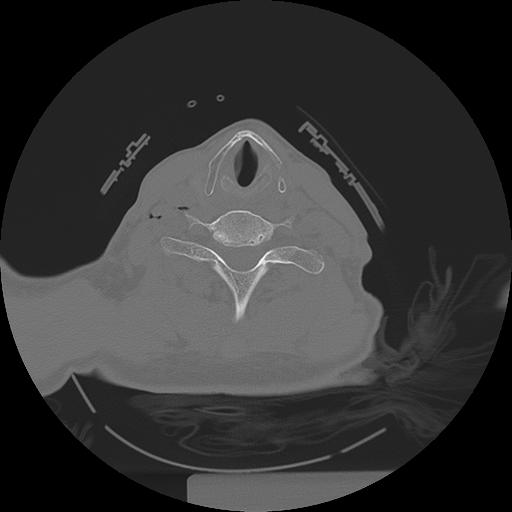

11 HUESO,,Axial,2.0,HUESO,,